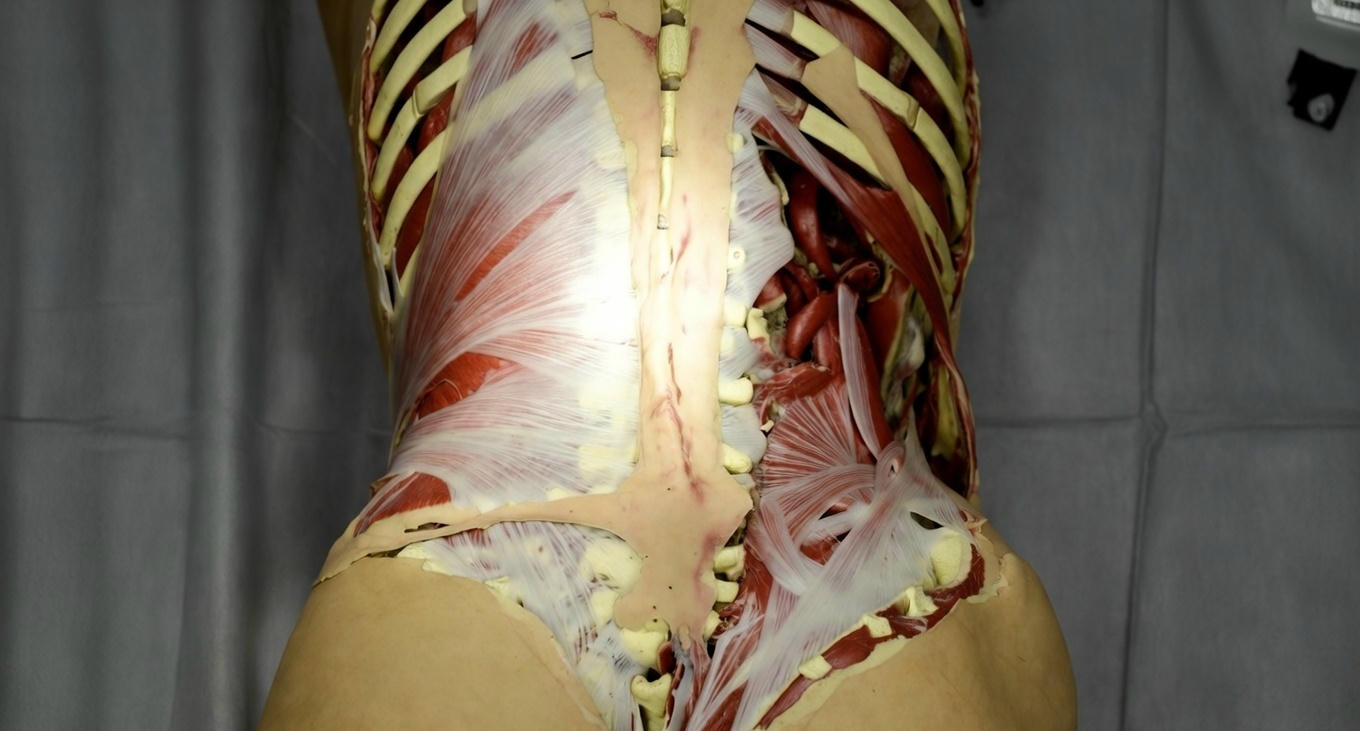

Fascia: The Mechanical Foundation

Let's begin with the dial that lies at the heart of everything we do at Physology: Fascia.

Fascia is your body's living, continuous web of connective tissue. It wraps every single muscle fibre, every nerve, every bone, every organ, forming one uninterrupted three-dimensional network from head to toe. It's richly supplied with nerves and plays an active role in how your body feels and moves.

When Fascia is healthy, it's full of water. Hydrated, elastic, and slippery, like a well-oiled sponge. Tissues glide past each other effortlessly, and movement feels free.

When Fascia becomes unhealthy, through injury, poor posture, repetitive strain, or chronic stress, the tissue dehydrates, thickens, and forms Fascia adhesions. Sticky spots where layers that should slide now grip and pull.

This pull doesn't stay in one spot. Because Fascia is interconnected, tension travels along the web. A restriction in your lower back can tug on your neck, shoulders, hips, even your hands, creating pain that seems to come from nowhere.

Researchers have found that the classic "tender points" used to diagnose Fibromyalgia are, in fact, active Myofascial Trigger Points. When these points are stimulated, they reproduce the entire spontaneous pain pattern of Fibromyalgia patients, not just local pain.

At Physology, we've seen this thousands of times: release the Fascial restrictions, and the pain map changes, often dramatically from the very first session. Fascia is the mechanical foundation of the State of Fibromyalgia and the first dial we turn down to bring you back to pain free.